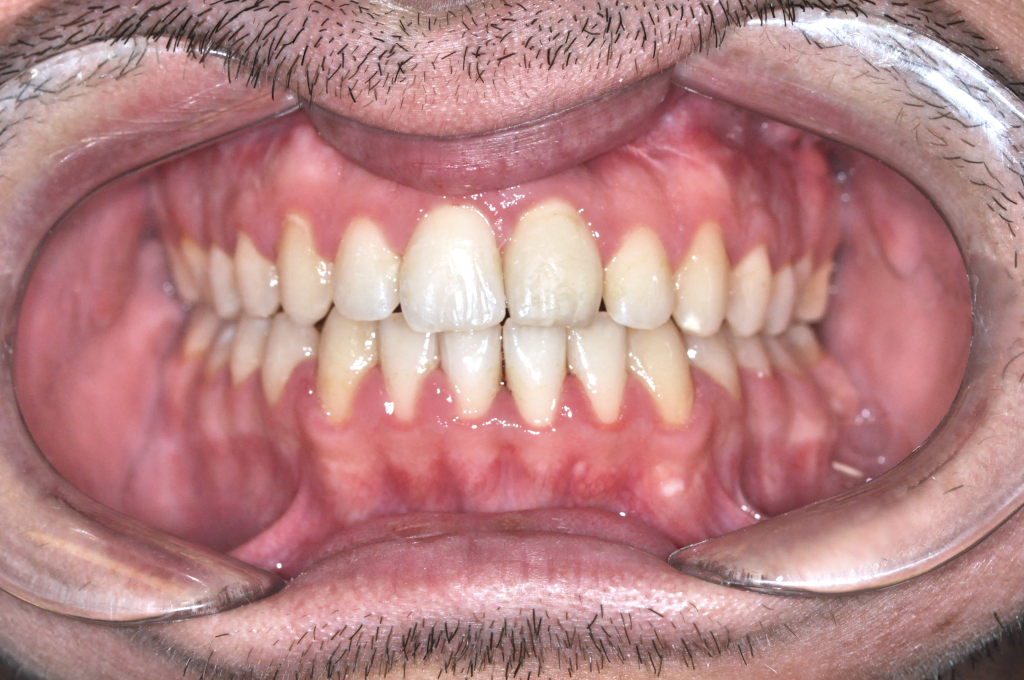

Utána fogsor - Bulldogharapás + nyitott harapás kombinált kezelése

Ebben az esetben két harapási rendellenesség volt jelen egyszerre.

Az alsó állkapocs előrehelyezett volt (bulldogharapás),

miközben elöl nyitott harapás alakult ki.

Ez állcsonti probléma volt, amely fogszabályozással önmagában nem kezelhető.

A kezelést fogszabályozással készítettük elő, majd az alsó állkapcsot kontrolláltan

hátramozgattuk,

a felső állkapcsot pedig előre és lefelé pozícionáltuk.

Eredmény: záró harapás, működő rágás, harmonikus arcprofil.